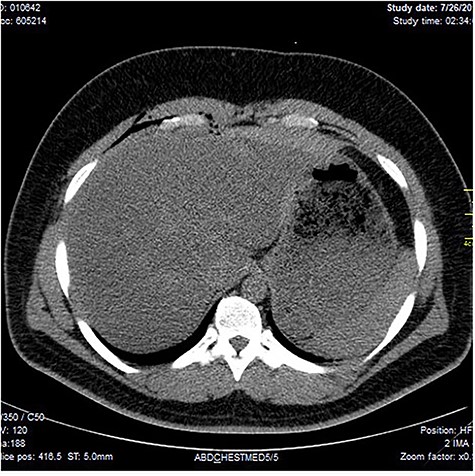

Chest X-ray was normal as shown in Fig. 1. Focused abdominal sonography for trauma (FAST) scan showed mild left perihepatic collection necessitating a thoracoabdominal computerized tomography (CT)-scan which showed external oblique muscle laceration with intermuscular air lucencies and grade 2 hepatic injury as shown in Figs 2–4. Other blood work-up were normal. No other injury was found on secondary survey. His wound was explored under local anaesthesia, primarily repaired, and he was discharged after 24 h of close observation.

Showing lucent air densities tracking through the right intercostal muscles and abutting on the liver in the epigastrum with associated subcapsular haematoma in the left lobe of the liver.

Image shows lucent air densities tracking through the subcapsular haematoma in the left lobe of the liver anterior to the pylorus of the stomach.